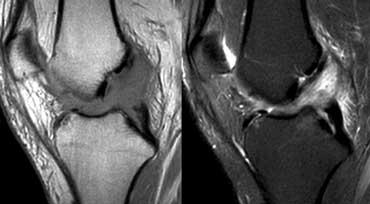

Cơ chế duỗi gối bình thường: Gân cơ tứ đầu đùi gồm ba lớp (mũi tên cam). Gân bánh chè (mũi tên xanh) và gân cơ tứ đầu đùi có ranh giới phía sau rõ nét.

Cơ chế duỗi gối bình thường

Cơ chế duỗi gối bao gồm cơ và gân cơ tứ đầu đùi, xương bánh chè và gân bánh chè.

Gân cơ tứ đầu đùi được cấu thành từ bốn gân nhưng hiển thị thành ba lớp trên ảnh mặt phẳng đứng dọc (sagittal).

Gân bám rộng từ mặt trước xương bánh chè gần đến mặt sau.

Các gân cơ tứ đầu đùi cũng như gân bánh chè có tín hiệu đồng nhất nhưng không nhất thiết phải đen trên ảnh chuỗi xung PD.

Chúng có ranh giới phía sau rõ nét.

Không nên có hiện tượng dày khu trú.